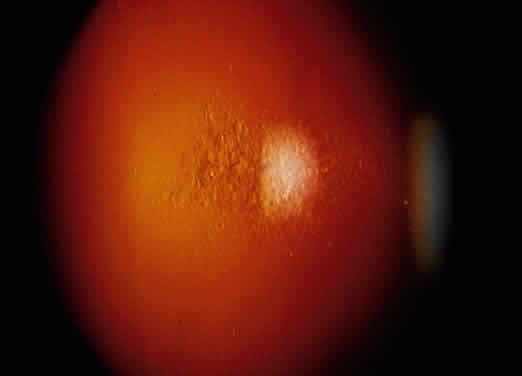

The intraocular inflammation may be acute, but more characteristically it is chronic and usually has few symptoms until vision is affected, or until significant structural changes have occurred. It may affect all parts of the eye. The chronic iridocyclitis is characterized by keratic precipitates that are well defined at the edges and tend to be more concentrated in the peripheral cornea (Fig. 8). The anterior chamber contains cells and flare, and the cells have a great tendency to form cellular nodules, either as keratic precipitates, precipitates on the iris, or at the pupil margin as Koeppe nodules (Fig. 9). The nodules tend to become the site of both peripheral anterior synechiae and posterior synechiae. The cellular reaction is usually sensitive to corticosteroids, but may recur as the corticosteroids are withdrawn.58,65 Treatment responses are further obscured by the frequent tendency for sarcoidosis to undergo spontaneous remission with time, and then recur at a later date. If oral steroids are indicated, moderate to low alternate-day dosages usually control the inflammatory process and produce less systemic side effects.

Fig. 9. Sharply defined Koeppe nodule in the pupil of a patient with ocular sarcoidosis.